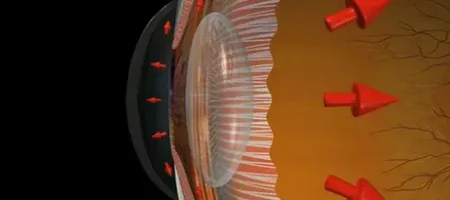

Glaucoma is an eye disease that collectively describes different eye conditions which affect the optic nerve and is often caused by internal eye pressure. This pressure buildup, known as intraocular pressure (IOP), damages the delicate fibers of the optic nerve over time. As the pressure continues to rise, it disrupts the normal flow of fluid within the eye, leading to gradual destruction of nerve tissue. The damage often begins in peripheral (side) vision and progresses inward, making it difficult for individuals to notice until significant loss has occurred. If left untreated, this can result in anywhere from mild vision impairment to severe and often irreversible blindness. Since glaucoma usually advances without warning signs, especially in the early stages, routine eye checkups are essential for early detection, monitoring, and treatment.

Primary open-angle glaucoma is the most common type of glaucoma and typically develops slowly over time. It occurs when the eye’s drainage canals become less efficient due to sclerosis of drainage system, leading to a gradual buildup of intraocular pressure. This pressure damages the optic nerve without causing noticeable symptoms in the early stages. Because of its silent progression, vision loss often goes undetected until it becomes more advanced. Regular eye examinations are essential to identify and manage this condition early.

Angle-closure glaucoma is a less common but more acute form of the disease. It occurs when the drainage angle of the eye becomes suddenly and completely blocked, causing a rapid rise in intraocular pressure. This can lead to severe eye pain, headache, nausea, and sudden vision loss. Because it progresses quickly, it is considered a medical emergency and requires immediate treatment. Prompt diagnosis is crucial to prevent permanent vision damage.